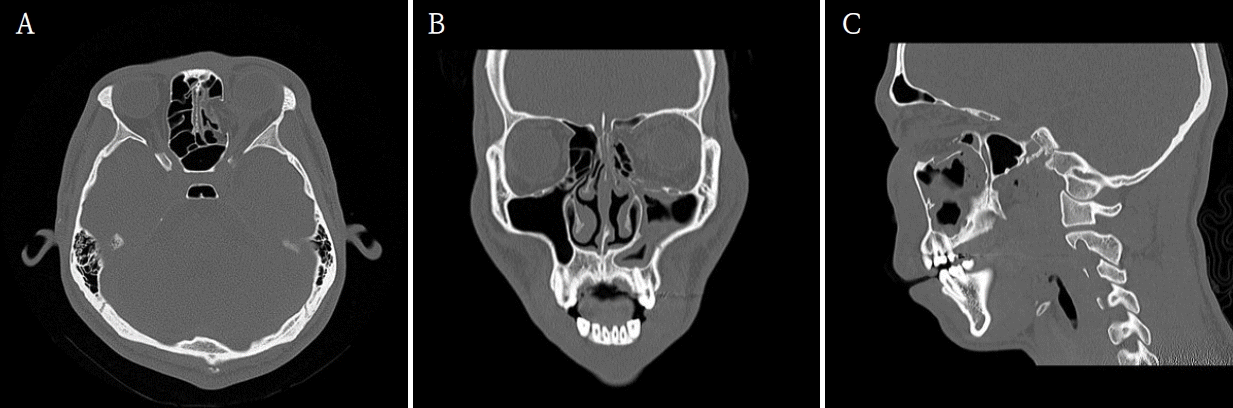

A 19-year-old male presented to the Emergency Department of Chonnam National University Hospital after sustaining facial trauma from slipping on the stairs. Severe swelling involving the left periorbital region and an approximately 2.0 cm laceration wound were observed on the left lower lip. The patient’s vital signs were stable, and neurological function was intact.Clinical examination revealed normal ocular motility, intact infraorbital sensation, and well-maintained globe position without diplopia or enophthalmos.A maxillofacial CT scan was performed for further evaluation. CT imaging demonstrated fractures of the left medial orbital wall, inferior orbital wall, and nasal bone (Fig. 1). The medial wall defect was located adjacent to the ethmoid sinus with partial herniation of orbital soft tissue. The inferior orbital wall fracture extended posteriorly with minimal displacement of the bony fragments, and a depressed nasal bone fracture was also confirmed.Initial management included primary closure of the lower-lip laceration under local anesthesia. Reduction of the orbital and nasal bone fractures was performed under general anesthesia using a multidisciplinary approach involving the Departments of Otorhinolaryngology and Oral and Maxillofacial Surgery.First, the medial orbital wall was repaired by the otorhinolaryngology team using an endoscopic transnasal approach with a navigation system (Fiagon Navigation System, Fiagon GmbH, Hennigsdorf, Germany). After uncinectomy and anterior ethmoidectomy, additional posterior ethmoidectomy was performed, followed by widening of the frontal and sphenoid ostia. This provided a clear surgical field for orbital compression and visualization of the left medial orbital wall fracture site (Fig. 2). The medial wall showed diffuse destruction with generalized herniation of the periorbita. After careful reduction of the herniated contents, a customized silastic sheet was inserted in an inverted U-shape (Fig. 3).Subsequently, the oral and maxillofacial surgery team performed intraoral access for reconstruction of the orbital floor. A vestibular incision approximately 3 cm in length was made, extending from the left canine to the first molar region. A bony window measuring approximately 15 × 10 mm was created in the anterior wall of the maxillary sinus to provide direct visualization of the inferior orbital wall defect. Herniated orbital tissue was carefully repositioned into the orbital cavity, and the orbital floor was anatomically reconstructed. A titanium miniplate with screws (DePuy Synthes, Oberdorf, Switzerland) was applied across the fracture line to achieve rigid fixation (Fig. 4). Layered closure was then performed to ensure proper wound healing and anatomical restoration.Finally, closed reduction of the nasal bone fracture was performed to restore nasal contour and symmetry. To maintain medial wall reduction and provide uniform compression, Merocel® (Medtronic Xomed, Jacksonville, FL, USA) was inserted into the ethmoid cavity. The operation proceeded smoothly without intraoperative bleeding, orbital content injury, or infraorbital nerve disturbance, indicating stable surgical control.Immediate postoperative CT confirmed successful reduction of both fractures. The patient experienced complete resolution of diplopia and ocular discomfort, while infraorbital sensation remained mildly decreased but improving. At two weeks, Merocel® packing was removed, and routine dressing was performed. At two months, follow-up CT and endoscopic examination demonstrated stable reconstruction, and the silastic sheet was removed (Figs. 5 and 6). The patient’s sensation had nearly recovered, and postoperative outcomes remained stable with preserved ocular movement, normal globe position, and proper occlusion.

Figure 5.

Postoperative computed tomographic (CT) images confirm successful reconstruction of the left medial and inferior orbital walls. A. Axial image shows restoration of the orbital contour with no residual herniation. B. Coronal image demonstrates stable support of the medial orbital wall and proper positioning of the orbital soft tissues. C. Sagittal image confirms an anatomically reconstructed orbital floor with maintained height and continuity.